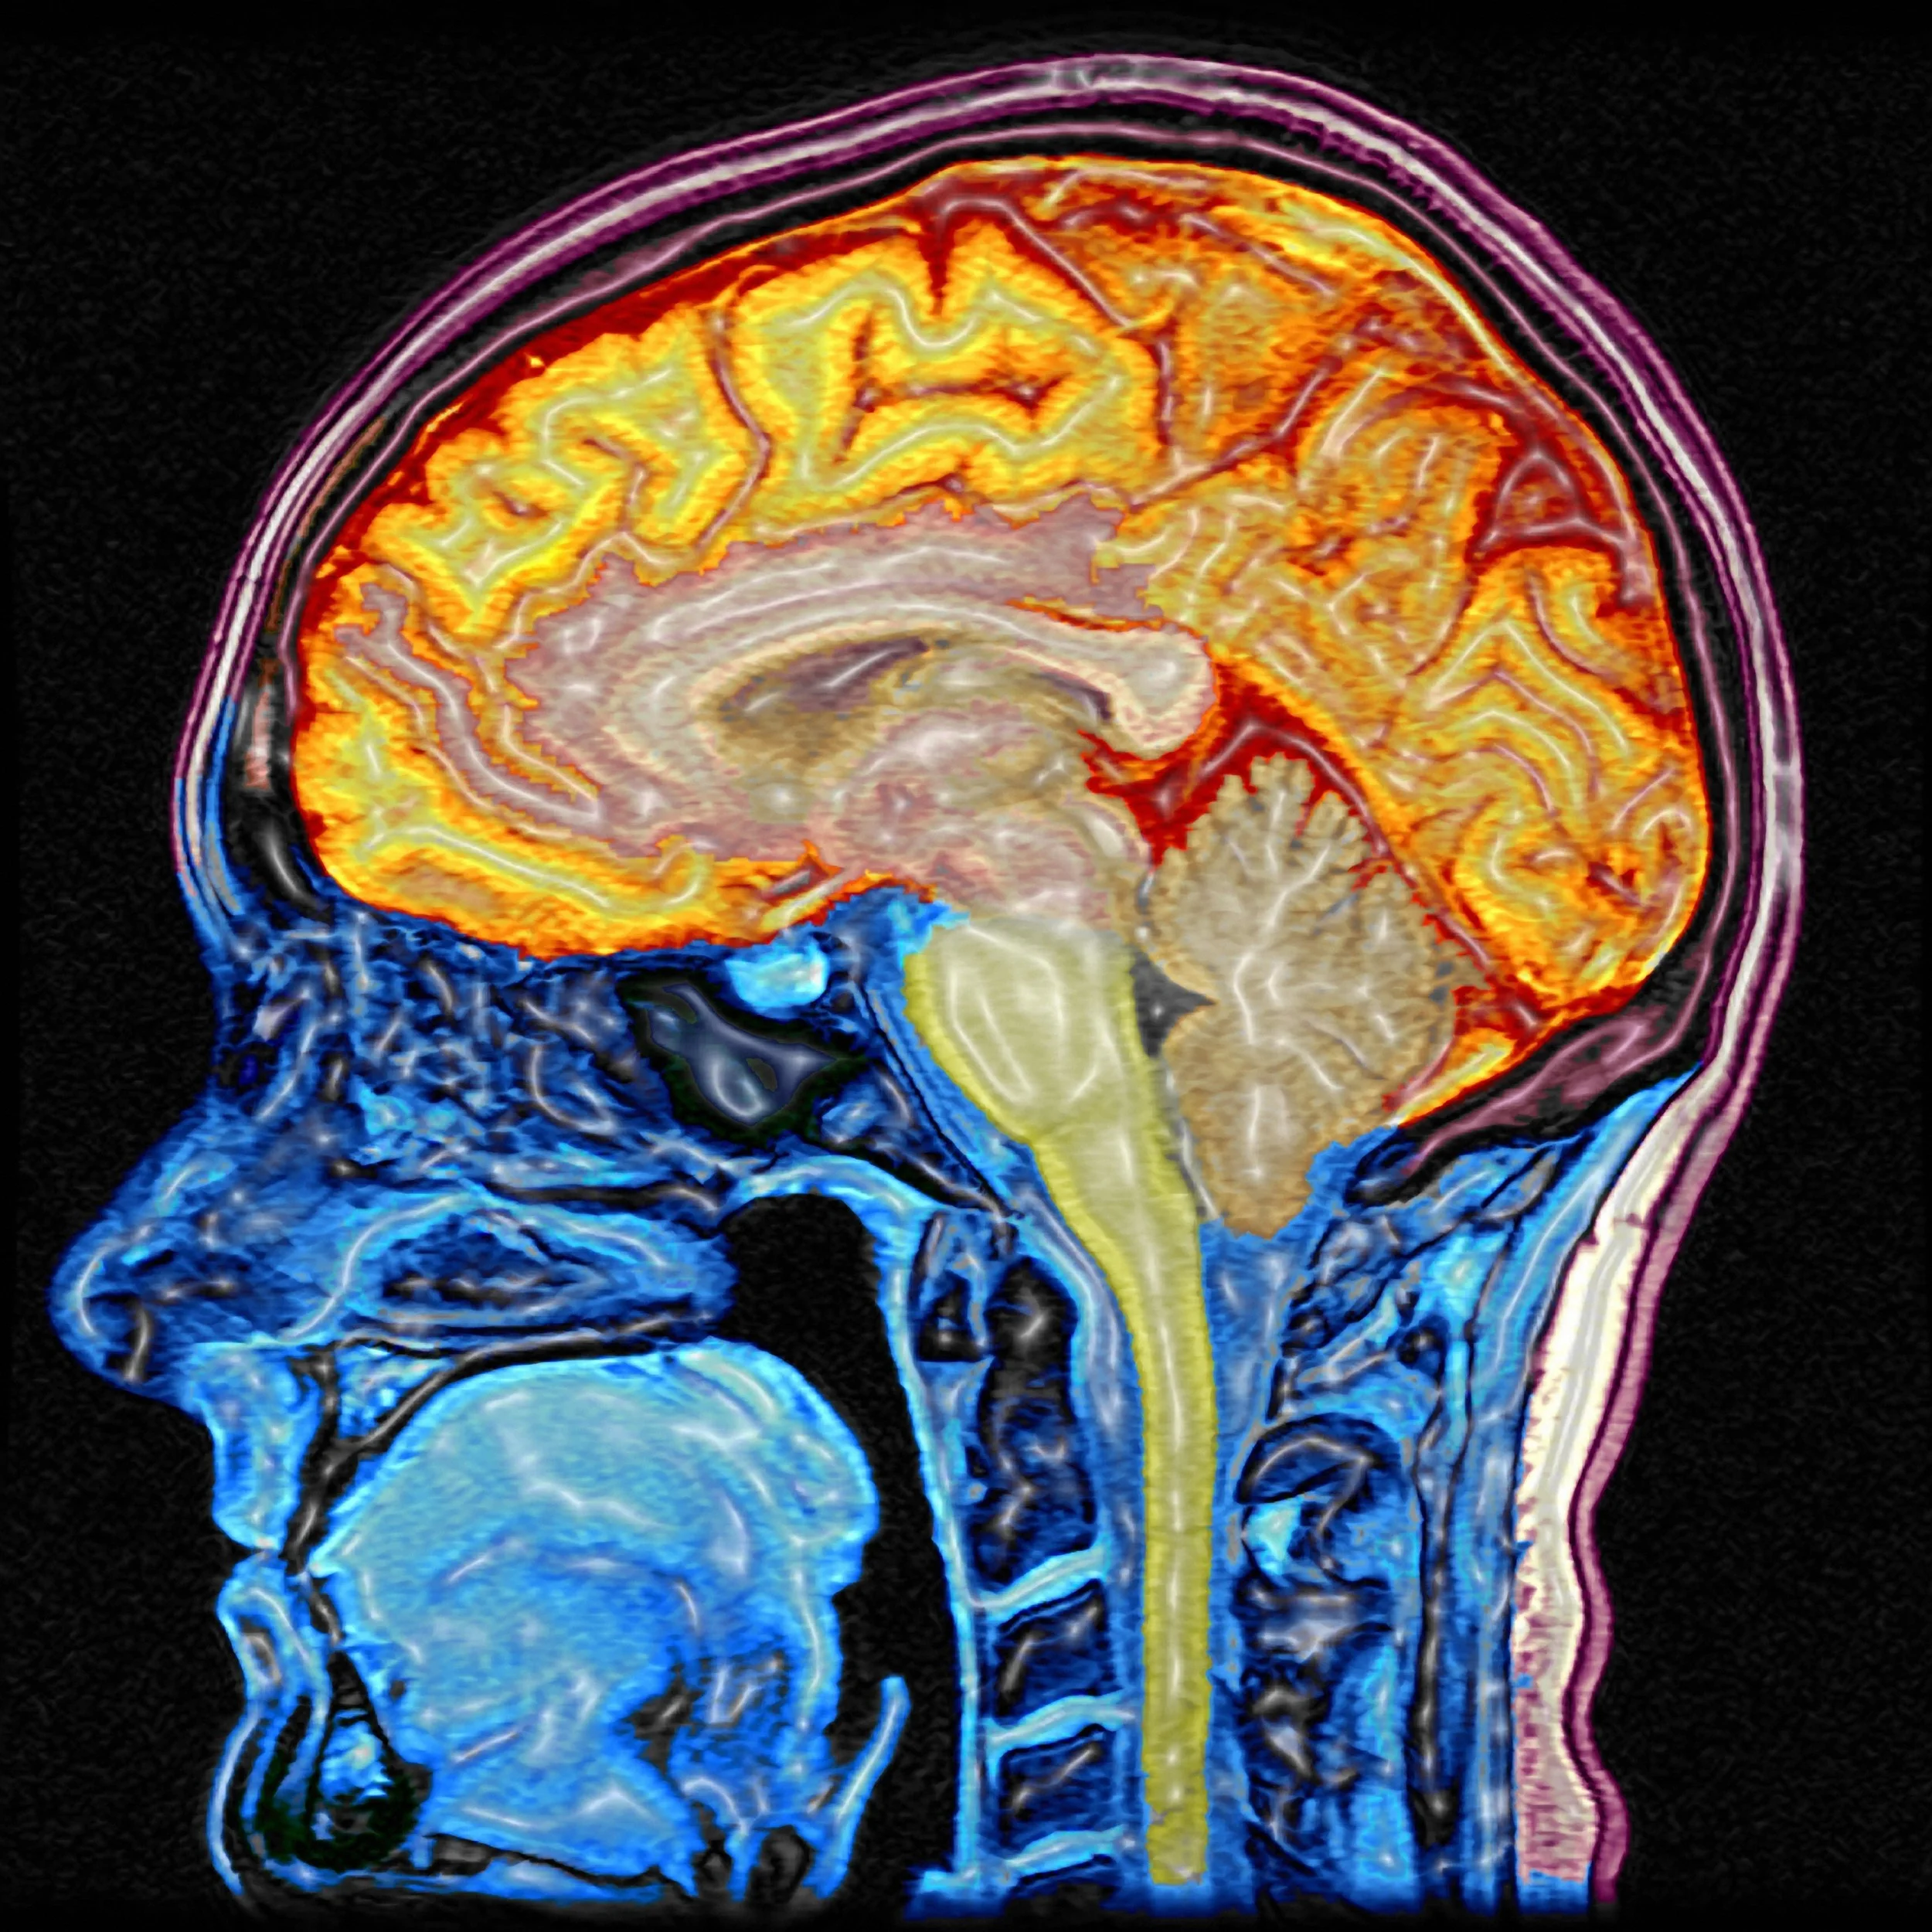

Фото Голов Мозга

Фото Голов Мозга 141 фотографий